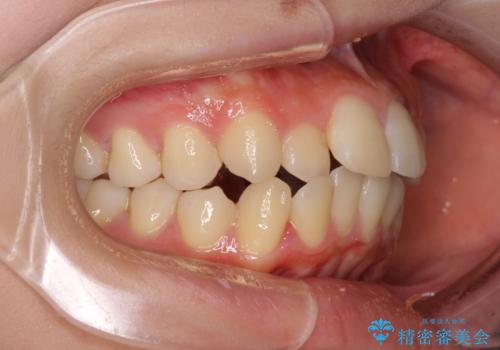

- 口元の閉じにくさを気にして来院された患者様です。

上下ともに歯列が前方に突出していたため、上下左右の第一小臼歯4本を抜去し、ワイヤー装置による矯正治療を行うこととしました。